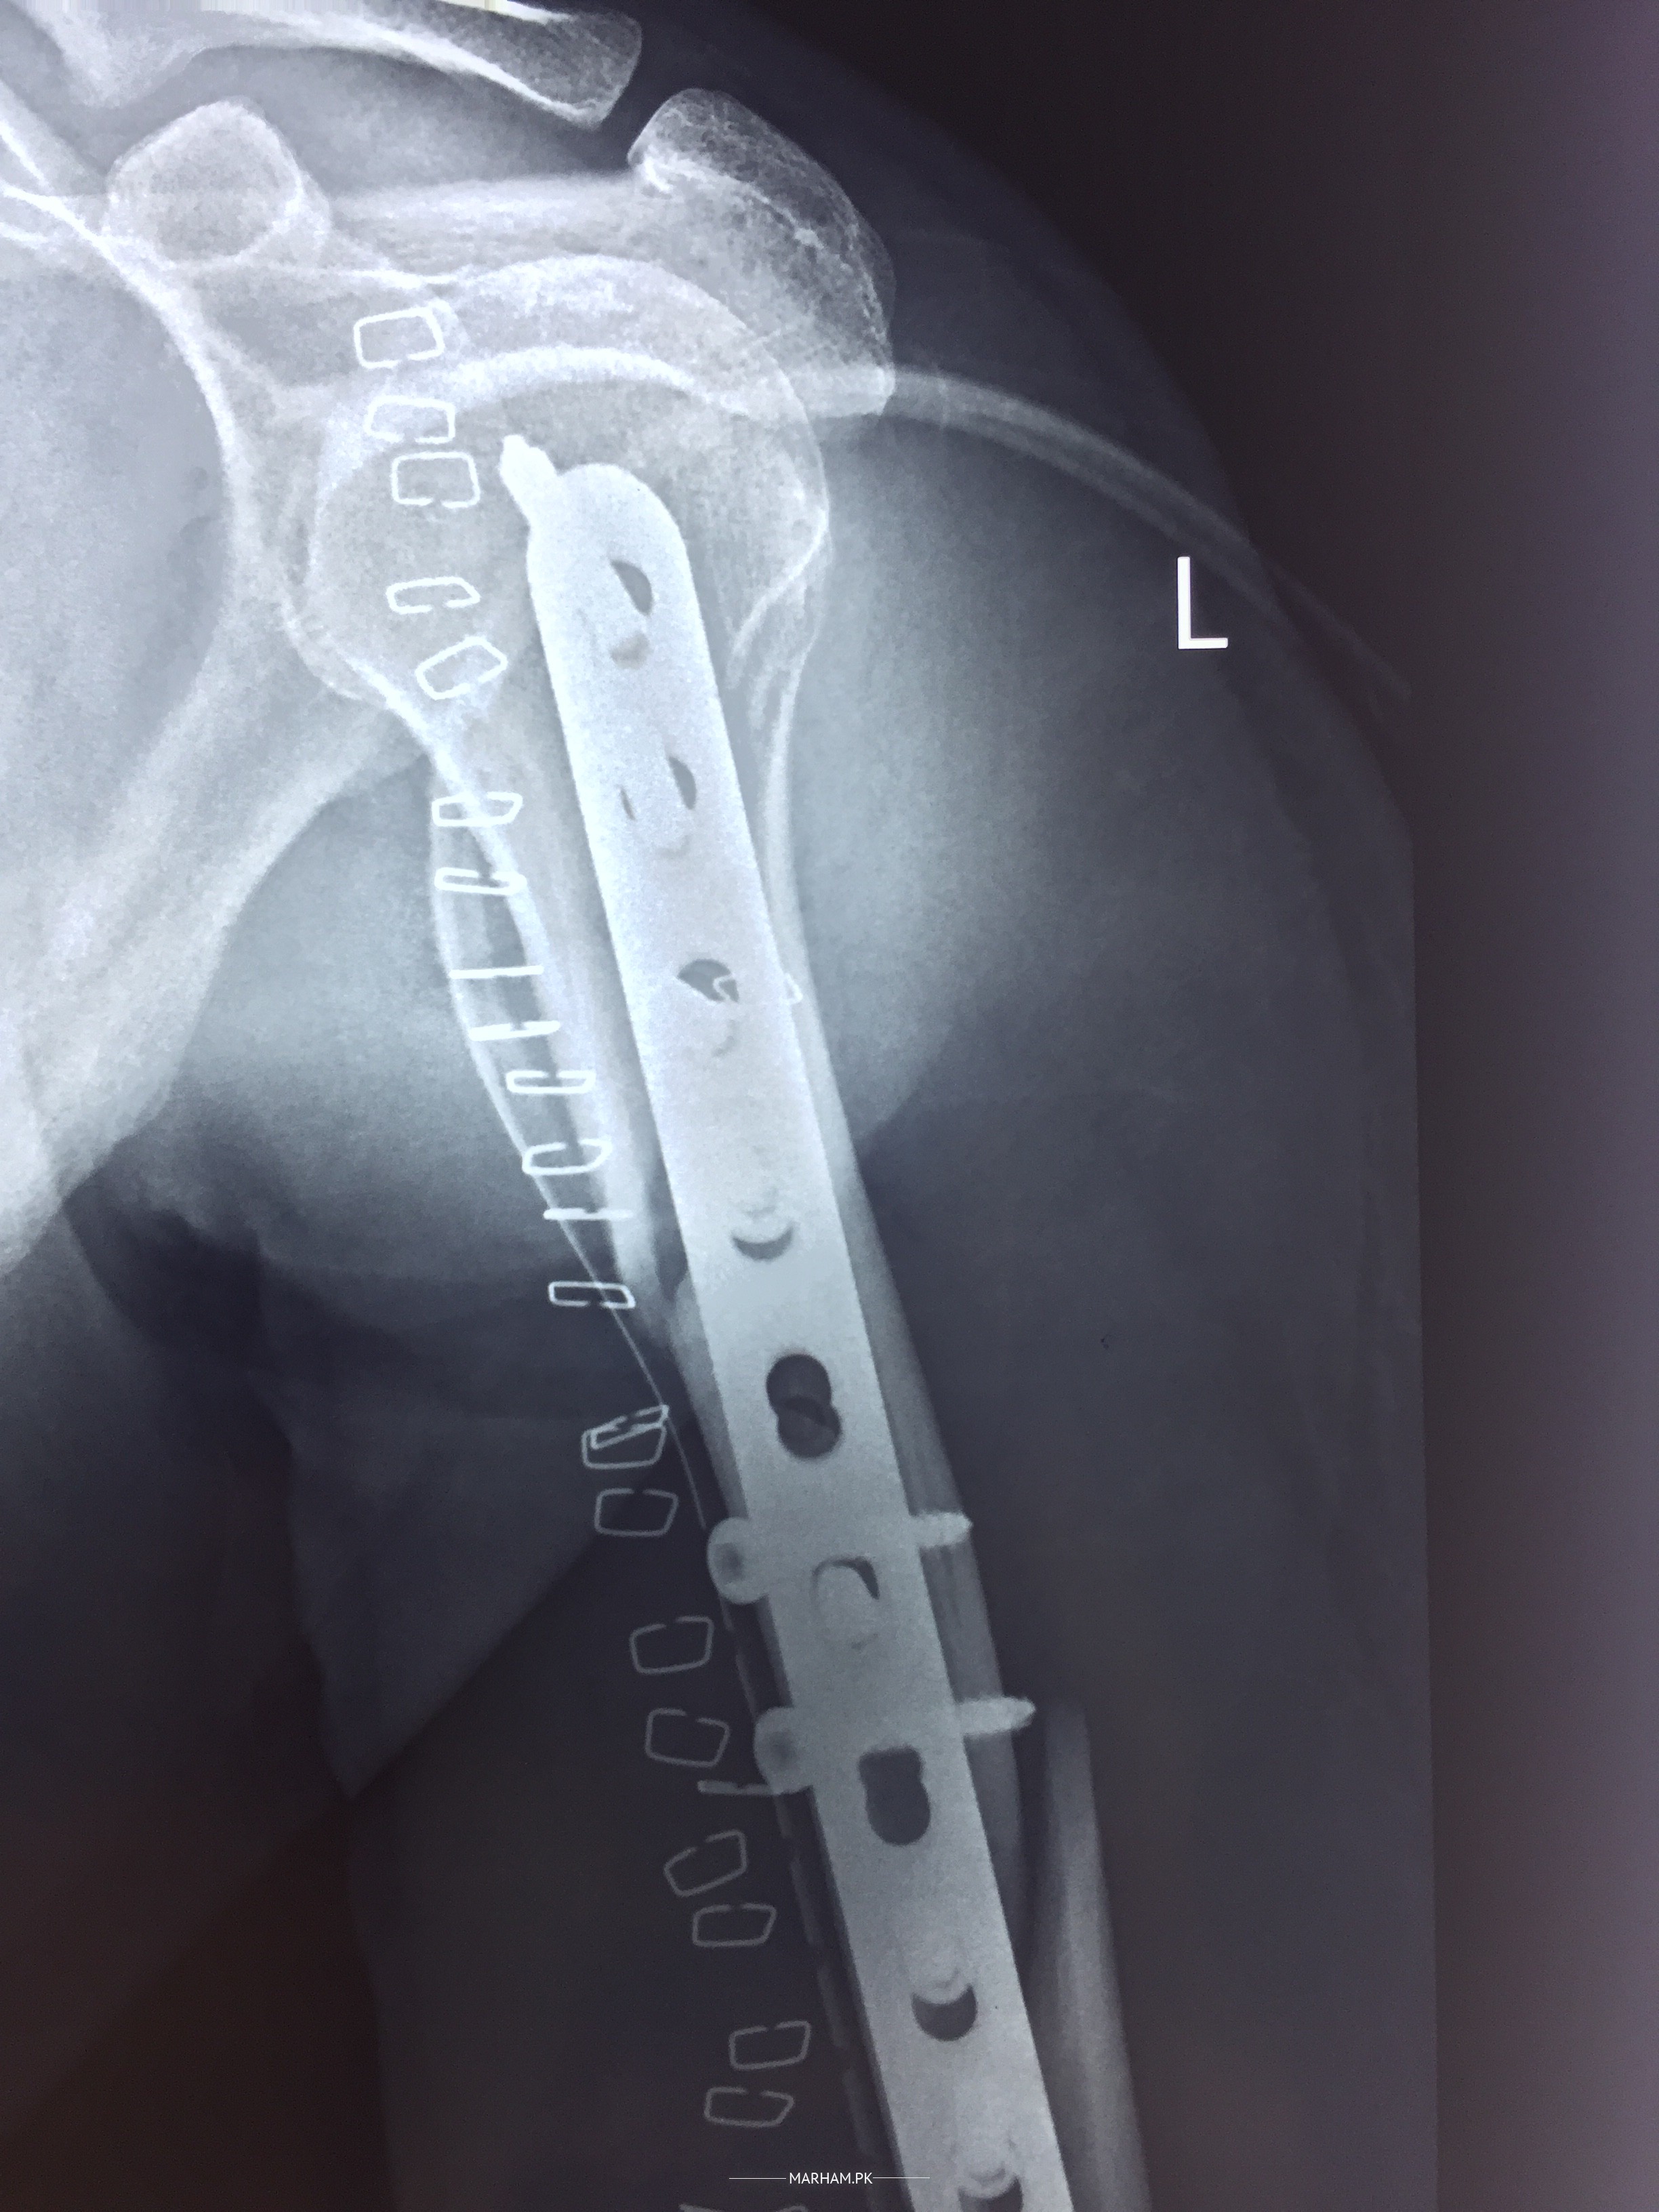

Attached are the pre surgery and post surgery X-ray images. is every thing fine

xrays are looking fine.

its a big surgery. two to three weeks of pain is normal.

make sure that wound is ok and no discharge or pus in the wound